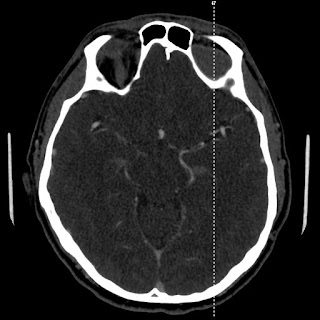

| Traumatic SAH |

![]() |

| Left anterior SDH |